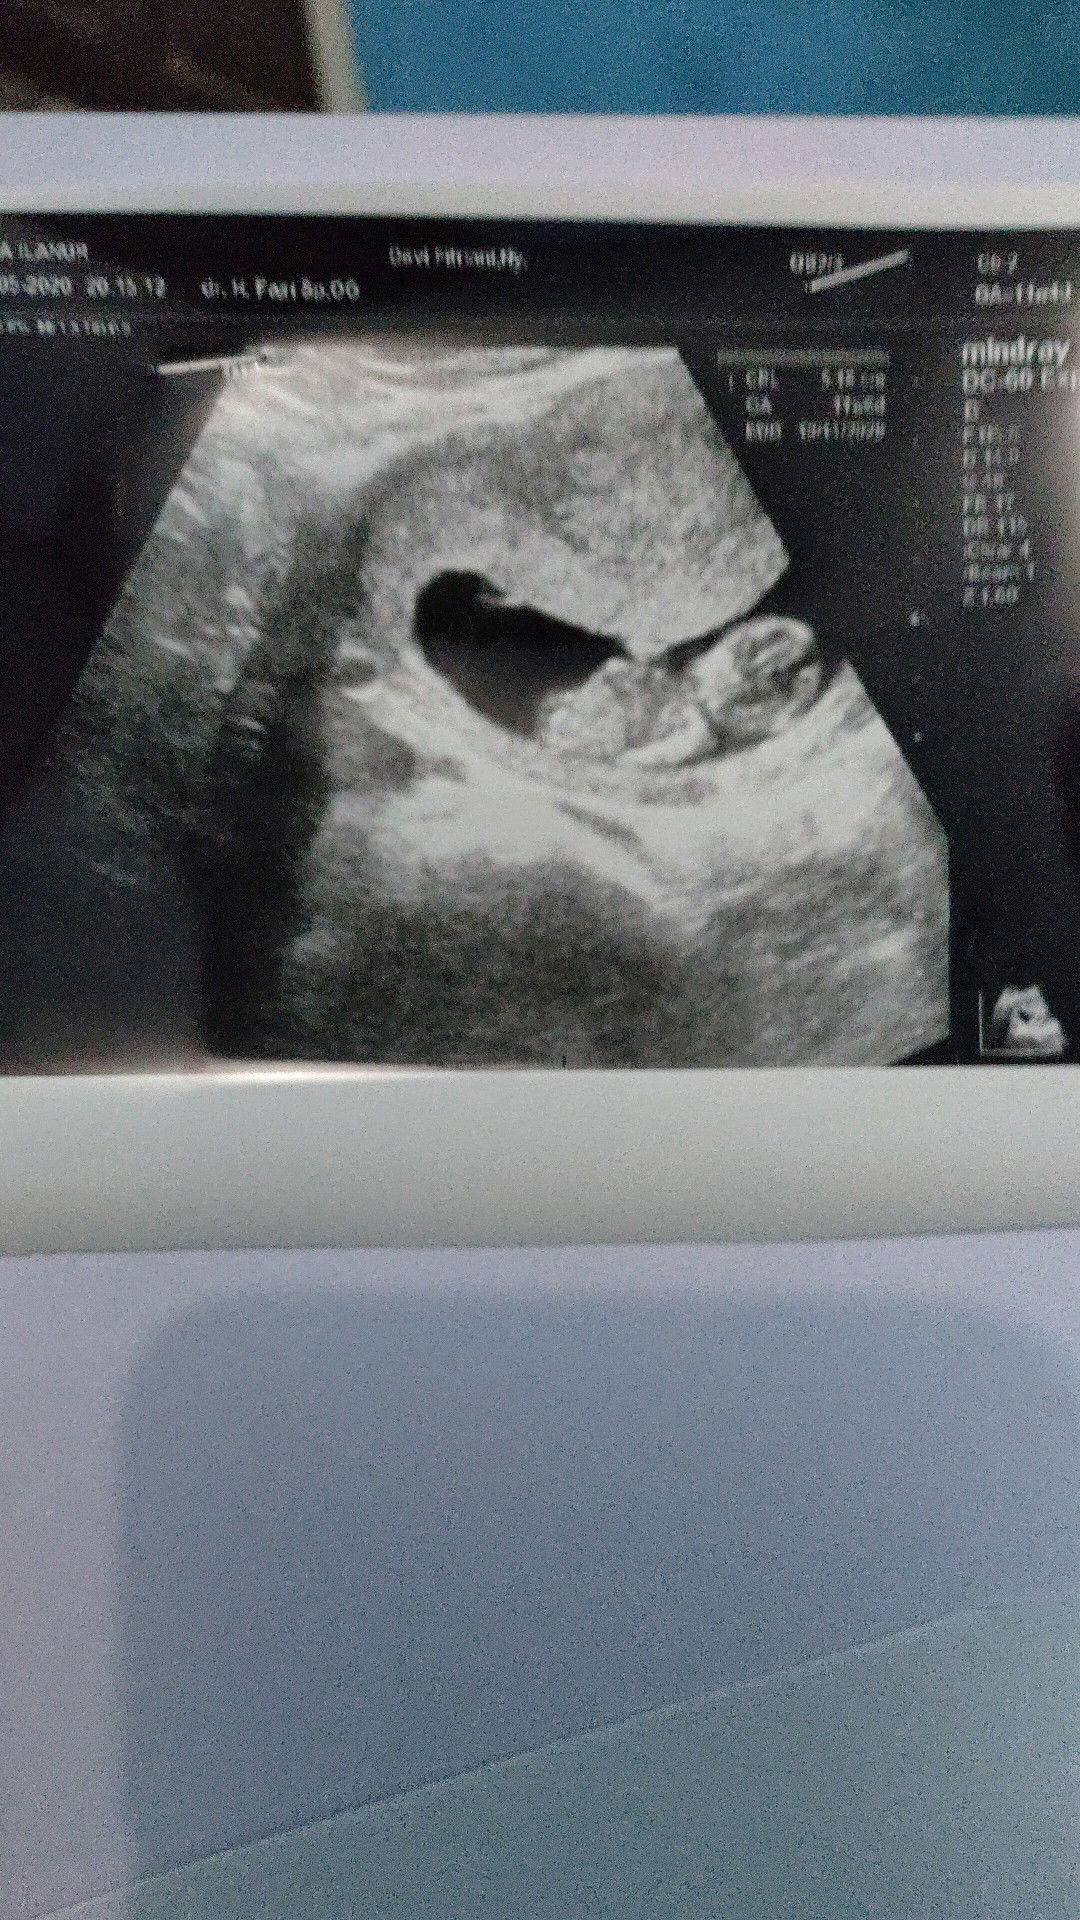

11week

alhamdulillah bun janin ny udah keliatan masyaalloh seneng ny maklum hamil yg kamren BO bun mohon doa ny yaa bun semoga lancar sampe lahirann,,??